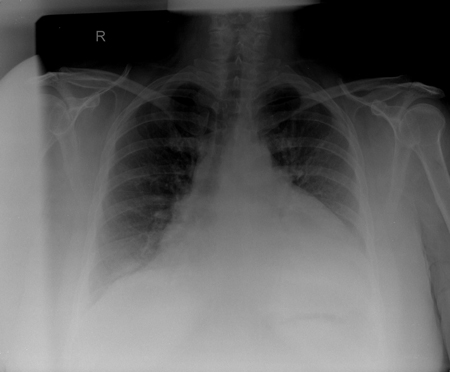

Chest radiography

A chest x-ray may show a water-bottle-shaped cardiac silhouette with a distinct pericardial fat stripe, suggesting a large pericardial effusion. Pleural effusions may also be present. [Figure caption and citation for the preceding image starts]: CXR in a patient with a pericardial effusion showing typical findings of a water-bottle-shaped cardiac silhouette with a distinct, fat, pericardial fat stripeFrom the collection of Dr Rajdeep Khattar [Citation ends].